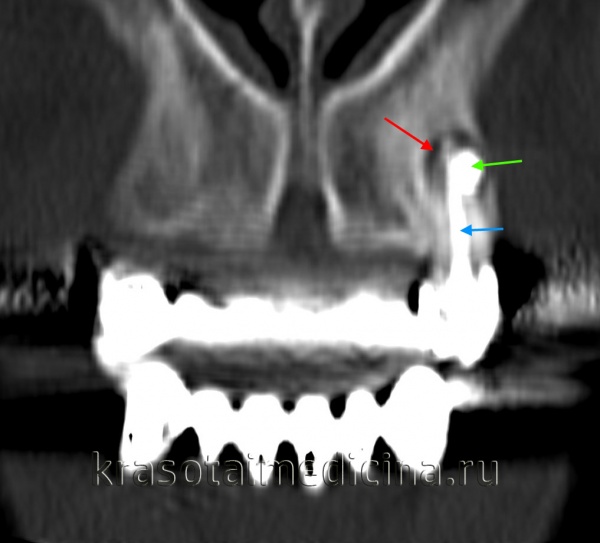

(Слева) При аксиальной КТ в костном окне визуализируется мелкая периапикальная радикулярная киста возле корня центрального резца верхней челюсти справа. Признаков периостальной реакции или наличия объемного образования в мягких тканях за пределами челюсти не определяется.

(Справа) При сагиттальной КТ у этого же пациента визуализируется периапикальная киста и стоматологическая амальгама в этом же зубе.

КТ челюстно-лицевой области. Радикулярная киста (красная стрелка) вблизи корня левого клыка верхней челюсти, состояние после эндодонтического лечения (синяя стрелка – филлер в корневом канале), избыток филлера за пределами верхушки зуба (зеленая стрелка).